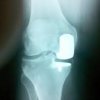

Blue Belt Technologies has treated the first three US patients for unicondylar knee replacement (UKR), using its NavioPFS orthopedic surgical system.

The UKR procedures, performed at the US-based Community Regional Medical Center, includes two left-medial and one right-medial partial knee replacement surgeries.

The system, which integrates CT-free navigation with intraoperative registration and planning, uses robotic handpiece to make less-invasive incisions and allows for precise and repeatable bone preparation while treating patients with medial osteoarthritis.